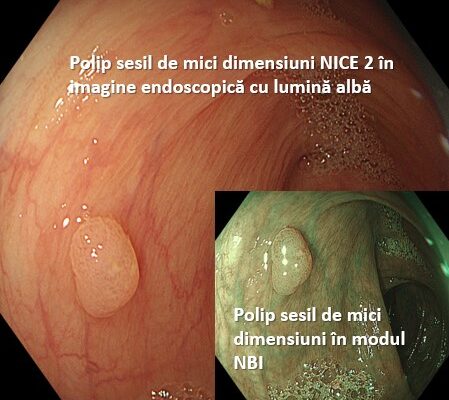

COLONOSCOPIA CU POLIPECTOMIE ÎN SCREENING-UL CANCERULUI COLORECTAL

În țările care au programe naționale de screening al cancerului colorectal mortalitatea cauzată de cancerul de colon este în scădere odată în urma utilizării colonoscopiei cu polipectomie. Majoritatea polipilor de colon sunt mici (< 1 cm) și pot fi îndepărtați...